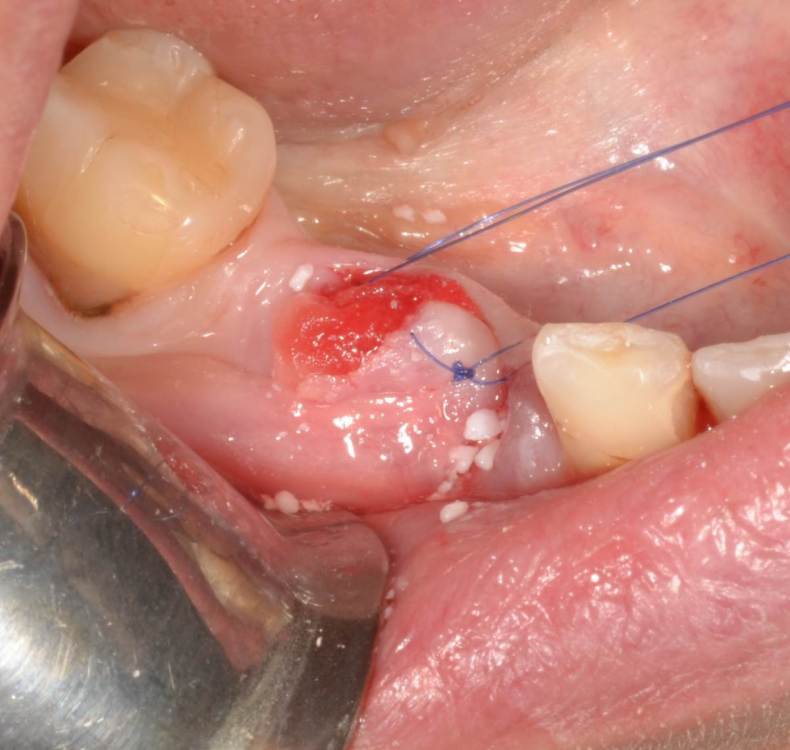

Большой Зеленый Опубликовано 27 мая, 2022 Поделиться Опубликовано 27 мая, 2022 Аналогично..) 4 1 Ссылка на комментарий

Большой Зеленый Опубликовано 27 мая, 2022 Поделиться Опубликовано 27 мая, 2022 Через 9 лет. Есть немного рецессии.. 2 Ссылка на комментарий

Женька Опубликовано 27 мая, 2022 Поделиться Опубликовано 27 мая, 2022 @Большой Зеленый это вроде ваш старый кейс? напомните пожалуйста, тут присыпка+мембранинг вестибулярно и вестибулярным лоскутом слегка послабленным всё закрыли? Ссылка на комментарий

Большой Зеленый Опубликовано 28 мая, 2022 Поделиться Опубликовано 28 мая, 2022 12 часов назад, Женька сказал: @Большой Зеленый это вроде ваш старый кейс? напомните пожалуйста, тут присыпка+мембранинг вестибулярно и вестибулярным лоскутом слегка послабленным всё закрыли? Да все так и есть как Вы и описали. Работе почти 10 лет. Присыпка мп3 от остеобила сверху "ильгамовская" губка . Считаю что результат вполне удовлетворительный. Рецессия обусловлена как уже сказали выше вестибулярным положением импланта ,ну и недозаглублен чуток. Ссылка на комментарий